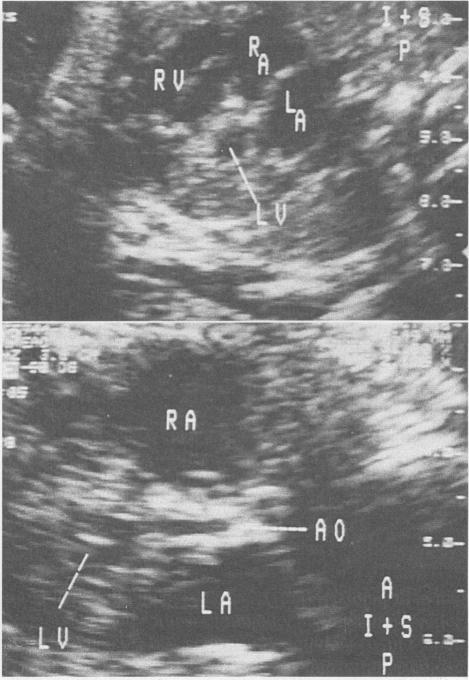

心脏超声检查在结构性异常和心律失常中的应用。识别与治疗。

Cardiac ultrasonography in structural abnormalities and arrhythmias. Recognition and treatment.

Fetal cardiac ultrasonography has become an important tool in the evaluation of fetuses at risk for cardiac anomalies. It can both guide prenatal treatment and assist the management and timing of delivery. We recommend that a fetal echocardiogram be done when there is a family history of congenital heart disease; maternal disease that may affect the fetus; a history of maternal drug use, either therapeutic or illegal; evidence of other fetal abnormalities; or evidence of fetal hydrops. The optimal timing of evaluation is 18 to 22 weeks' gestation. An entire range of structural cardiac defects can be visualized prenatally, including atrioventricular septal defect, ventricular septal defect, cardiomyopathy, ventricular outlet obstruction, and complex cardiac defects. The outcome for a fetus with a recognized abnormality is unfavourable, with less than 50% surviving the neonatal period. Fetal cardiac arrhythmias are also a common occurrence, 15% in the series described here. Premature atrial or ventricular contractions are most commonly seen and usually require no treatment. Supraventricular tachycardia can result in hydrops and require in utero treatment to prevent fetal demise. Complete heart block, particularly in association with structural heart disease, has a poor prognosis for fetal survival.

胎儿心脏超声检查已成为评估有心脏异常风险胎儿的重要工具。它既可以指导产前治疗,又有助于分娩的管理和时机选择。我们建议,当存在先天性心脏病家族史、可能影响胎儿的母体疾病、母体有治疗性或非法药物使用史、其他胎儿异常证据或胎儿水肿证据时,应进行胎儿超声心动图检查。最佳评估时机是妊娠18至22周。产前可以看到一系列结构性心脏缺陷,包括房室间隔缺损、室间隔缺损、心肌病、心室流出道梗阻和复杂心脏缺陷。已确诊异常的胎儿预后不佳,新生儿期存活率不到50%。胎儿心律失常也很常见,在此系列研究中占15%。最常见的是房性或室性早搏,通常无需治疗。室上性心动过速可导致水肿,需要宫内治疗以防止胎儿死亡。完全性心脏传导阻滞,尤其是与结构性心脏病相关时,胎儿存活预后不良。